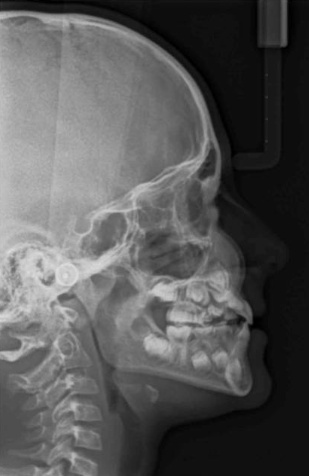

Le cabinet est équipé d’un appareil radiologique KODAK 8000 ceph permettant la réalisation de panoramique et de téléradiographie nécessaires à la réalisation des bilans orthodontiques et au suivi thérapeutique. Ces radiographies numérisées sont de qualité optimale avec des doses minimales d'irradiation.